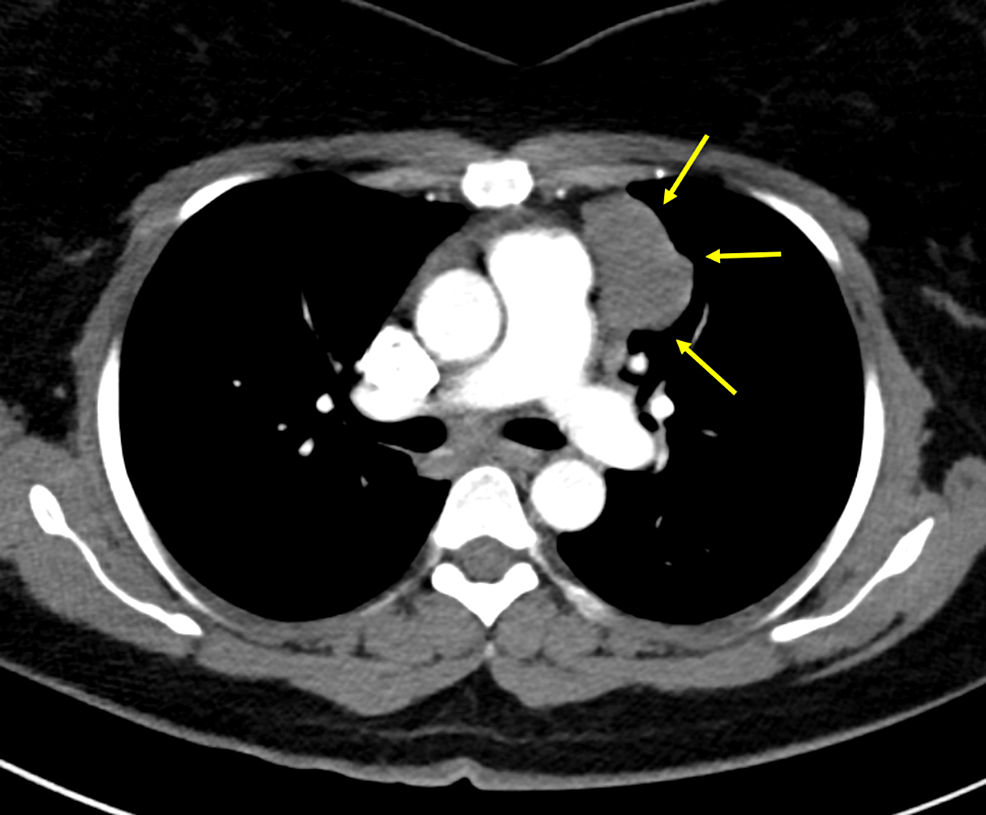

From www.clinicalradiologyonline.net

Imaging of thymus in myasthenia gravis From thymic hyperplasia to What Is The Connection Of The Thymus Gland To Myasthenia Gravis What is the connection between the thymus gland and myasthenia gravis? Several arguments show a strong association between the thymus and myasthenia gravis (mg). In many adults with myasthenia gravis, the. A thymectomy treats problems with your thymus gland, such as: The thymus gland grows gradually until. Many people with myasthenia gravis have thymus gland conditions that may trigger. Disease. What Is The Connection Of The Thymus Gland To Myasthenia Gravis.

From www.semanticscholar.org

Figure I from Computed Tomography of the Thymus Gland in Myasthenia What Is The Connection Of The Thymus Gland To Myasthenia Gravis Many people with myasthenia gravis have thymus gland conditions that may trigger. What is the connection between the thymus gland and myasthenia gravis? Myasthenia gravis is an autoimmune disease mediated by antibodies against proteins expressed in the. Disease typically have clusters of immune cells. The thymus gland grows gradually until. In many adults with myasthenia gravis, the. Mg has a. What Is The Connection Of The Thymus Gland To Myasthenia Gravis.